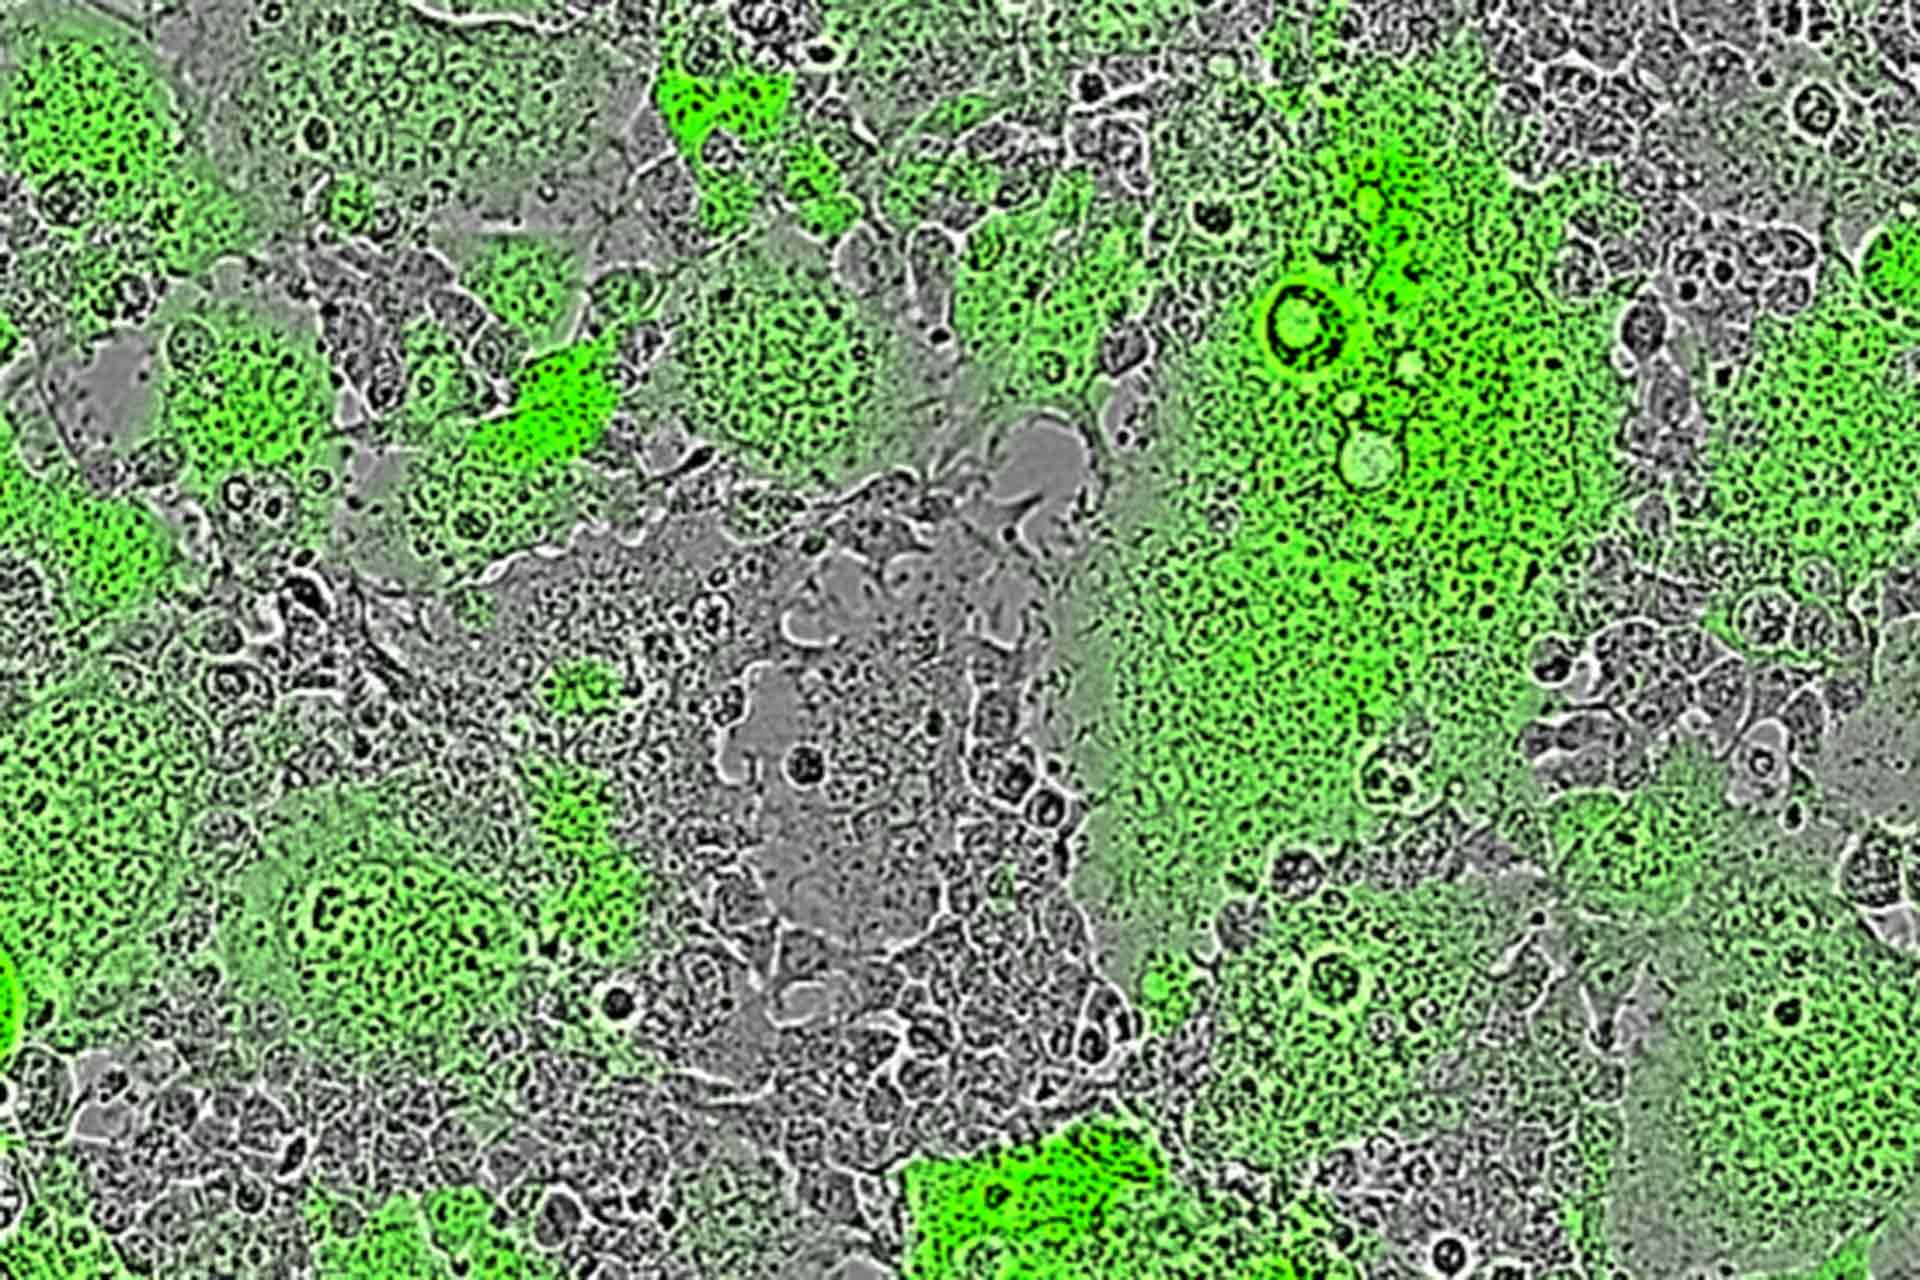

Image shows Nipah virus induced cell-cell fusion leads to the formation of fluorescent green syncytia (multi-nucleated cells) in Pirbright’s mFIT assay.

Most antibody tests focus on detecting neutralising antibodies, which block viruses from entering cells to prevent infection. However, some viruses have evolved a way to infect neighbouring cells without needing to form viral particles. Instead, their viral surface proteins recognise receptors on adjacent cells, forcing them to fuse together. This creates large cells with multiple nuclei, known as syncytia, and may allow the virus to spread in a way that avoids neutralising antibodies.

Cell fusion is used by viruses such as RSV and Nipah virus to spread, and there is growing evidence that SARS-CoV-2 can also cause syncytia formation. In their paper, the researchers demonstrated that the spike protein of SARS-CoV-2 can induce cell to cell fusion; however, the importance of this to natural infections remains to be determined. The immune response to these fusion events is poorly understood partly owing to the limited tools for investigating antibodies which may prevent syncytia formation.

The new method, named the micro-fusion inhibition test (mFIT), could be the very tool to fill this gap. Studies described in the Journal of General Virology demonstrate the test can be used in a variety of applications to assess whether antibodies can halt fusion events.